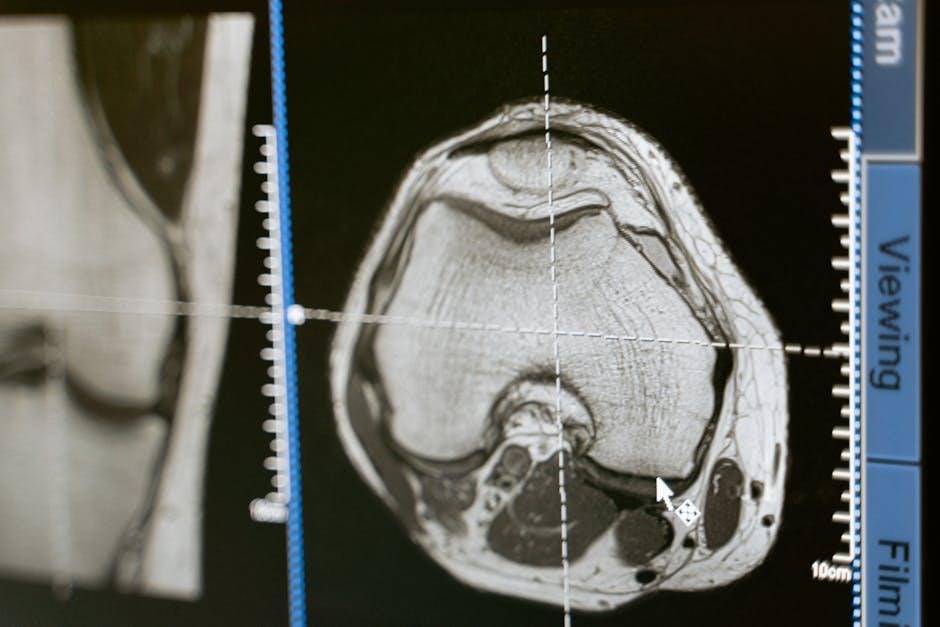

5․2 Musculoskeletal (MSK) MRI: Joints, Muscles, and Bones

MSK MRI is indispensable for evaluating joint injuries, soft tissue damage, and bone abnormalities․ It’s frequently used for diagnosing ligament and tendon tears, cartilage damage (meniscal tears), and bone fractures not readily visible on X-rays․ MRI excels in visualizing muscles, identifying strains, contusions, and masses․

However, judicious ordering is key, as overuse exists․ GP training and quality assurance initiatives are crucial for appropriate referrals, particularly with direct access pathways․ Guidelines emphasize correlating clinical findings with imaging requests․ Utilizing MSK MRI effectively requires careful consideration of patient history, physical examination, and established appropriateness criteria to optimize care․